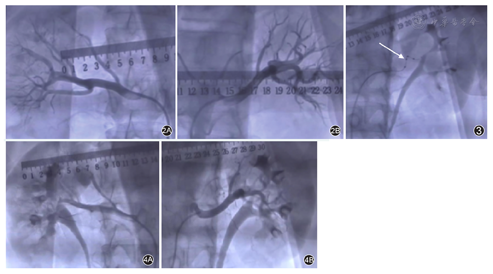

应用美国Medtronic公司Symplicity Spyral导管系统(图1),经股动脉入路实施。患者全身麻醉后,经右侧股动脉入路,使用6 F导管分别对右侧和左侧肾动脉进行造影,明确肾动脉血管走行和分支(图2)。

首先对左侧肾动脉进行消融。导丝顺利进入左侧肾动脉分支远端,沿导丝送入Symplicity Spyral导管,4个螺旋形分布的消融电极到位后,退出导丝,检查电极贴靠情况,调整电极贴靠良好后启动消融仪,以8 W功率完成左侧肾动脉的第1次消融60 s(图3)。并继续按由分支到主支,由远及近的顺序,继续完成左侧第2、3、4、5次60 s的消融。按同样策略,继续完成右侧肾动脉共计7次消融。左、右肾动脉合计消融位点48个。

消融完成后,复查双侧肾动脉造影(图4),肾动脉血管未见明显损伤,肾周无造影剂渗漏等,手术顺利结束。术中患者心率及血压平稳。